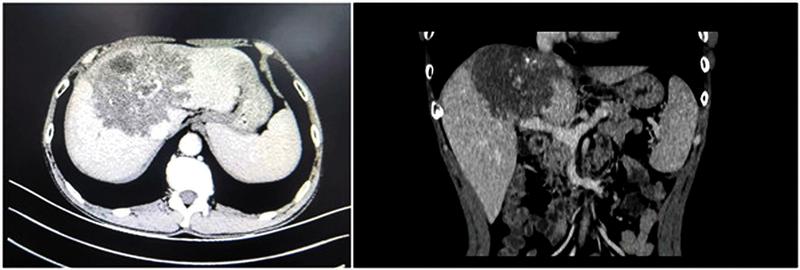

49岁的王先生来自乾县,近段时间无故出现上腹部胀痛,严重影响日常生活,当地县医院的检查结果为“肝脏巨大占位,考虑恶性肿瘤可能”。为了不耽误病情,王先生一家先后辗转多家医院,但均被告知肝脏肿块性质不明,且根据肿物侵犯情况,唯有行肝移植才可能带来治愈希望。经过多方咨询王先生的家人联系到了我院普通外科肝胆胰脾外科的陆宏伟教授。经过细致分析,陆宏伟教授考虑患者虽无牧区接触史,结合血清学及影像组学检查,系终末期泡型肝包虫病,保留侧肝体积足够,虽然第二肝门严重侵犯,但考虑到泡型肝包虫的侵袭性特征,下腔静脉在术中有可能从病灶上剥离,因此可考虑先行在体开腹探查,若确实无法在体切除,可转行离体肝切除自体肝移植术。

术前经过详细缜密的多学科病情讨论和组内商议,陆宏伟教授及团队成员一致认为终末期泡型肝包虫病诊断明确。其中病灶严重侵犯第一、第二、第三肝门,同时侵犯三支静脉的肝腔静脉汇合部,第二肝门水平下腔静脉环周侵犯240度,下腔静脉横向最大侵犯270度,纵向侵袭长度5cm;门静脉左支及右支起始部、右前分支侵犯;病灶侵犯S1、2、3、4、5v、8,若行上述肝段切除,剩余肝体积为546mL,占标准肝体积的47.6%>40%,因此是安全可行的,离体肝切除自体肝移植术是最合适的手术方案。但考虑到患者家庭经济情况,陆宏伟教授决定先行在体探查,若无法行病灶与下腔静脉分离,则行下腔静脉人工血管架桥,保留侧第二肝门重建,如若考虑出血风险无法控制或缺血时间超过肝脏耐受极限,则行离体肝切除自体肝移植术。术前充分与家属沟通病情及围术期风险等情况并取得知情同意后,手术如期进行。